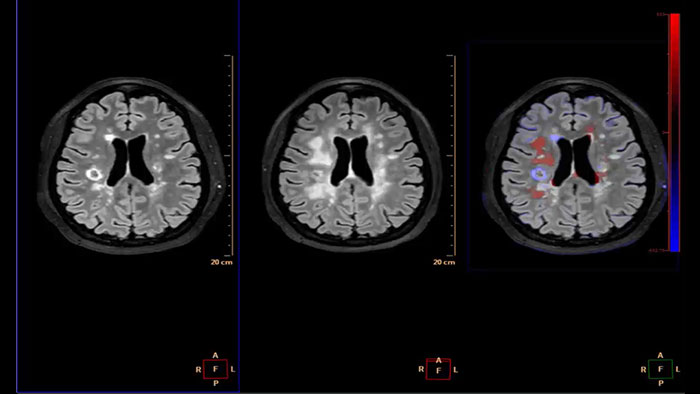

Computed diffusion weighted images at a b-value of choice

The application is intended to view, process and analyze MRI Diffusion Weighted Images. It calculates and displays cDWI at a

b-value of choice (from 0 to 5,000 s/mm2) and provides advanced supportive analysis and visualization tools of diffusion MRI images and parametric maps.